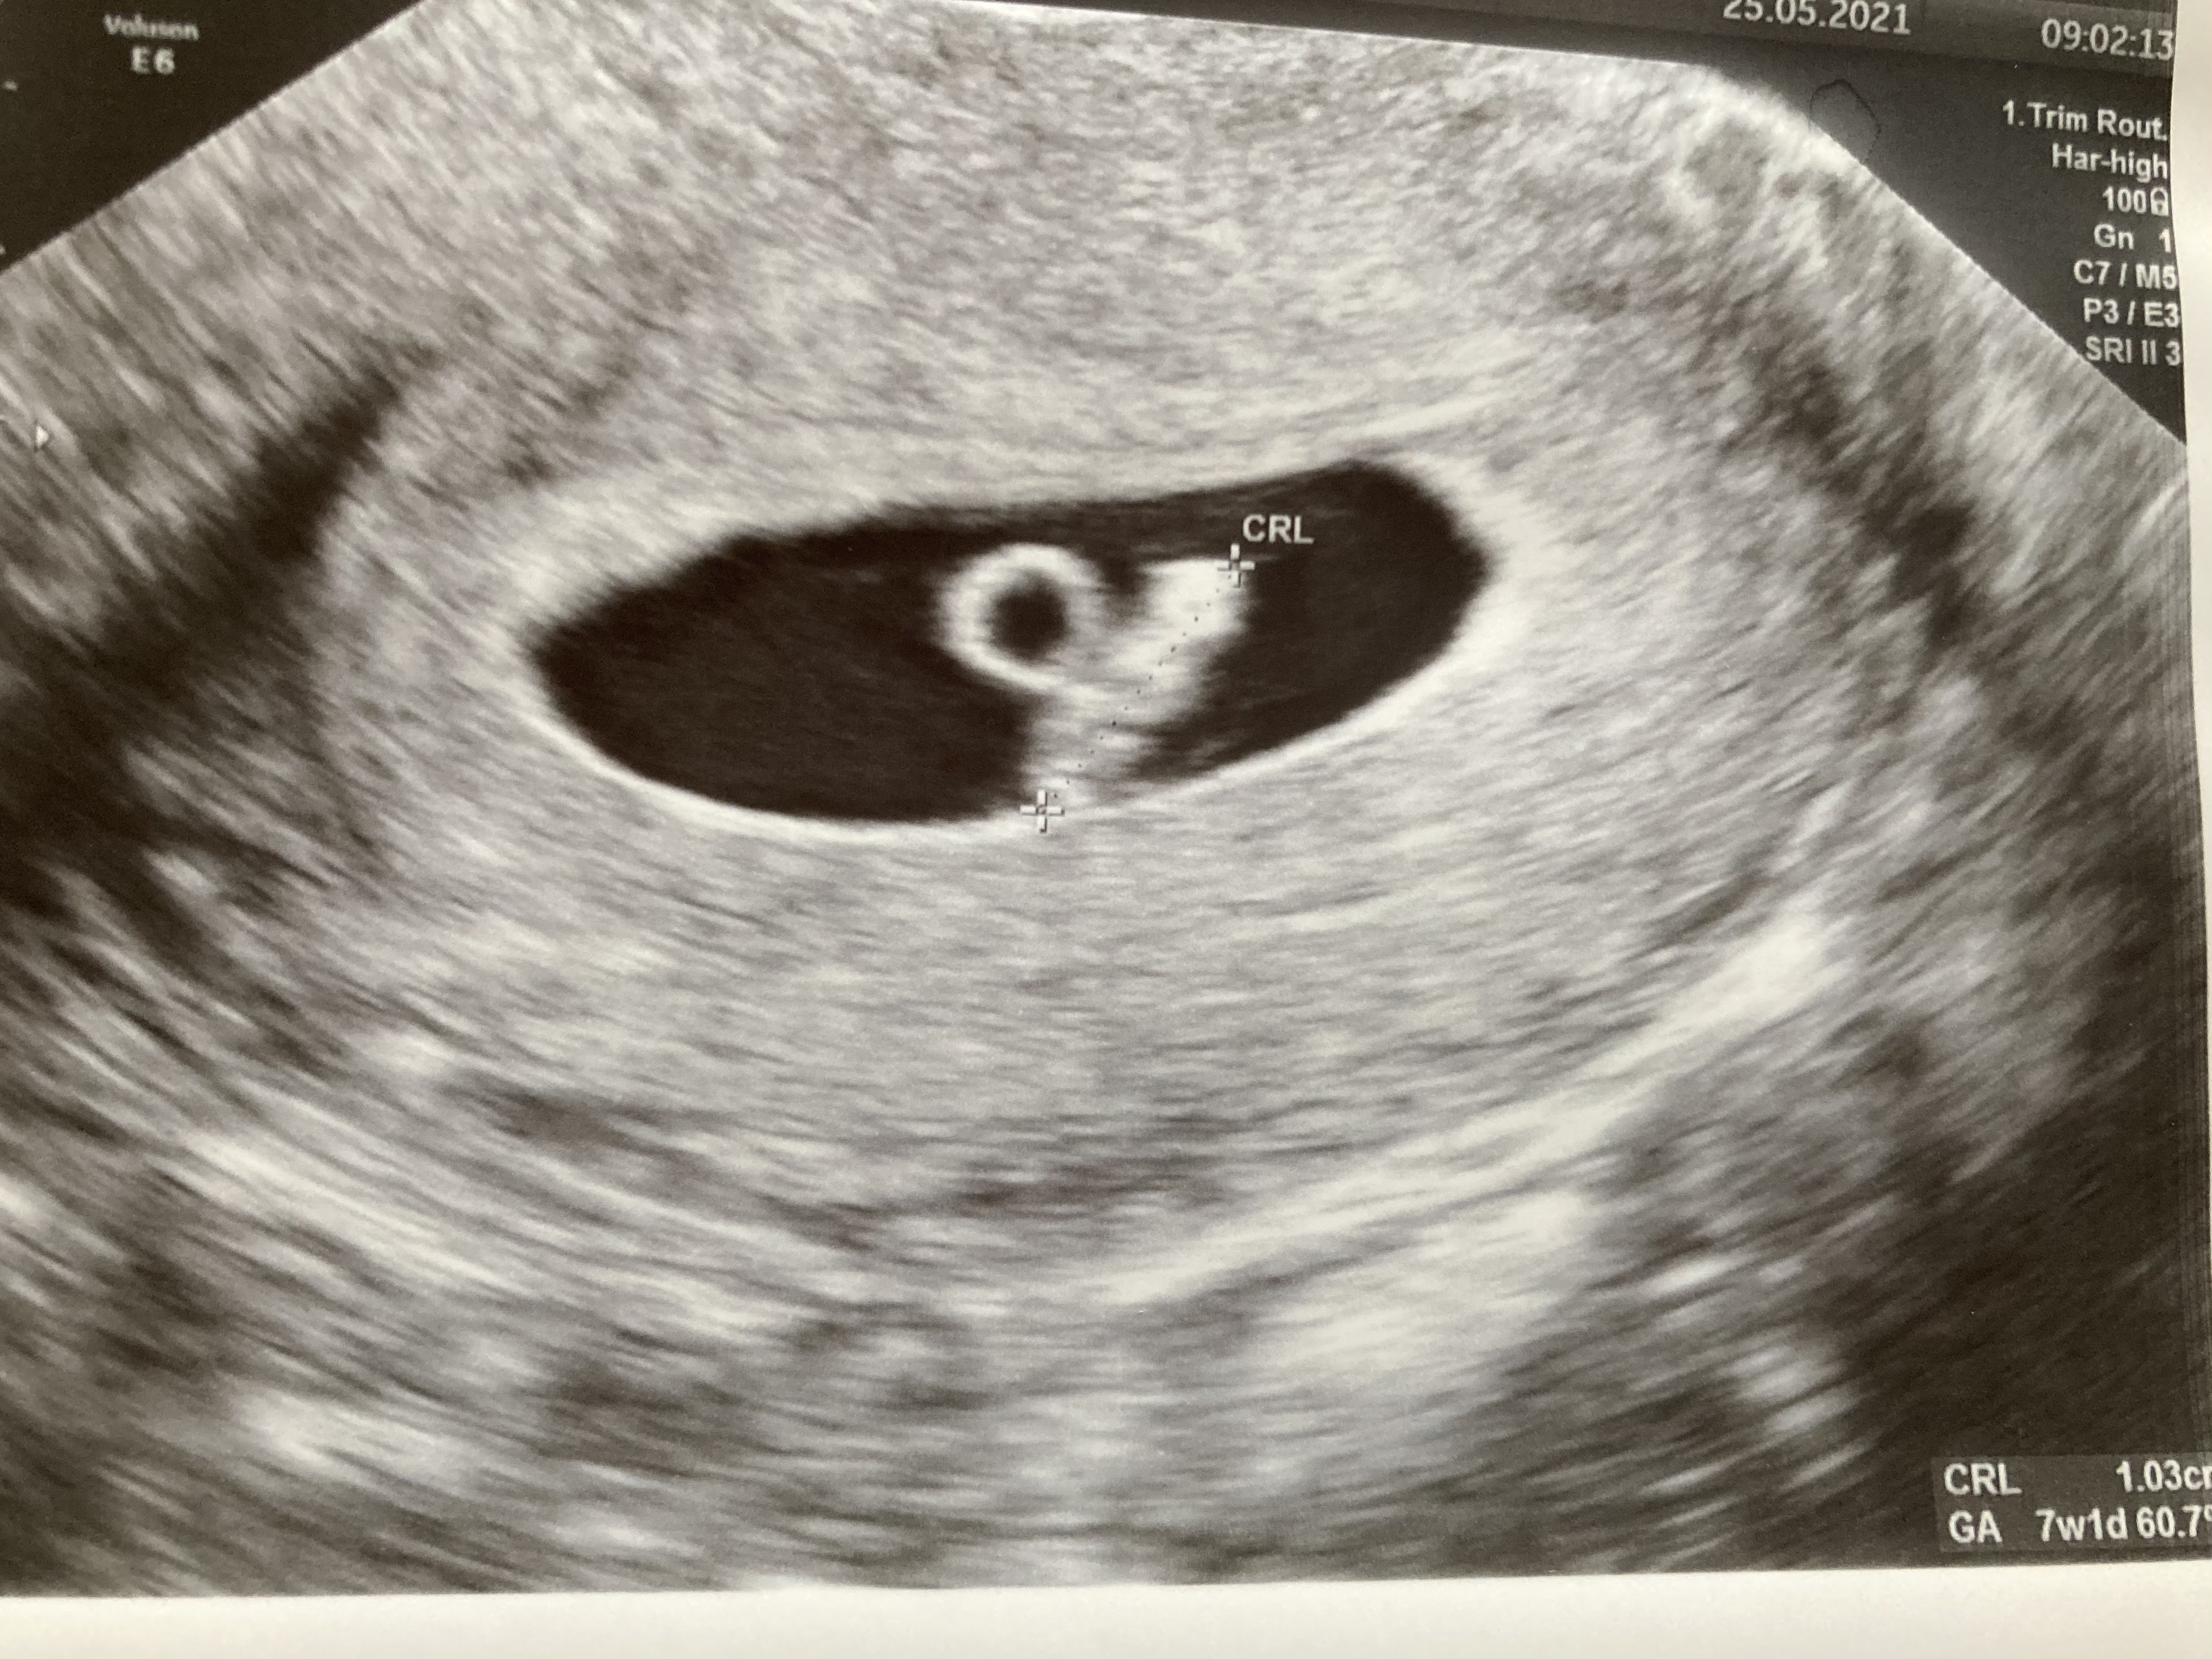

Wrzucam moje zdjęcie z 7+1. Zarodek 1cm, pęcherzyk ciążowy nie zmierzony, ale wygląda na ponad 3cm, także podobnie do tego u ciebie 😊 gdyby coś było nie tak, lekarz na pewno by powiedział :)